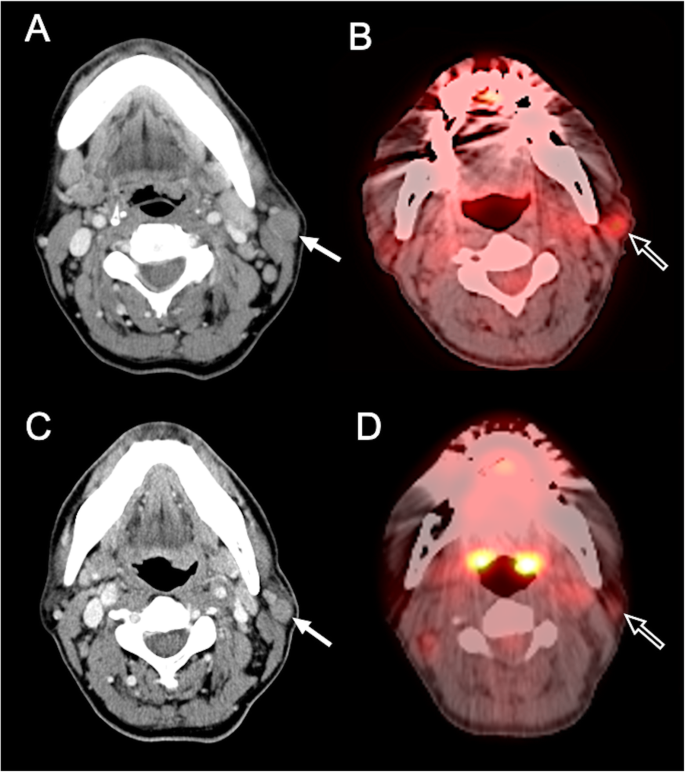

结果解读:新兴技术能早期检测治疗反应:例如DWI在脑胶质瘤中,低ADC值提示高细胞密度、预后差(图9,ADC=0.72×10⁻³mm²/sec的肿瘤3个月复发,而ADC=1.42×10⁻³mm²/sec的肿瘤72个月无复发);PET在霍奇金淋巴瘤中,SUV降低50%提示治疗有效(图11,预处理SUV=3.0,治疗后SUV=1.5,RECIST误判为无反应但PET提示有效)。

- 代谢学Biomarker(SUV、Cho/NAA):适用于免疫治疗,反映肿瘤代谢与增殖变化——例如在NSCLC中,PET的SUV降低提示免疫治疗有效。

- 淋巴瘤中,治疗后SUV降低≥50%的患者,客观缓解率(ORR)为82%,显著高于SUV降低<50%的患者(35%,P<0.001,图11)。